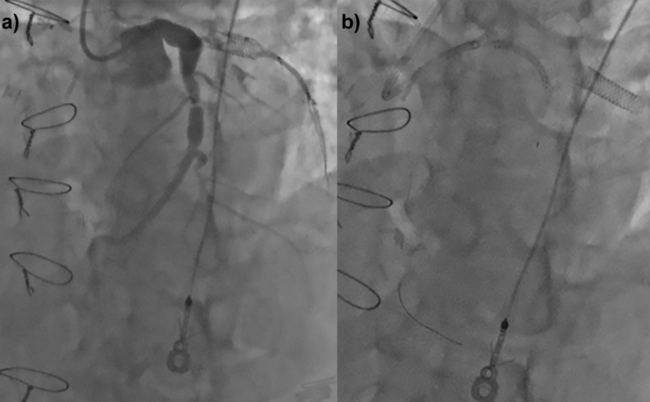

A patient with occluded bypass grafts underwent intervention for persistent angina. His left anterior descending artery was ectatic with severe mid-vessel disease (Figure 3a). A balloon-expanding 7.0- x 27-mm peripheral stent was dislodged off the balloon, proximal to the lesion, and could not be advanced (Figure 3b). It could not be deployed as it extended into the aorta. Another guidewire was placed through the struts and a 20-mm Amplatz Goose Neck snare (Medtronic) was advanced over both wires outside of the body to presnare. The snare was navigated around the stent (Figure 3c) and it was withdrawn (Figure 3d). The procedure was terminated (Video Series).